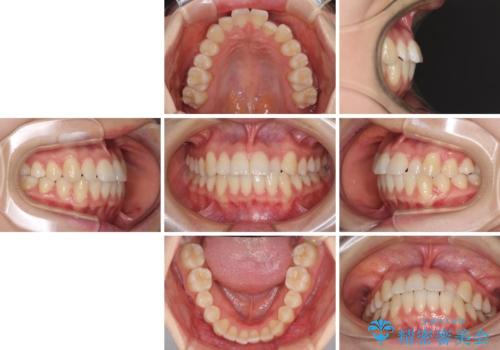

前歯のクロスバイト インビザラインによる矯正治療

- 前歯のクロスバイトを気にして来院された患者様です。

短期間での治療を希望され、ワイヤー装置とインビザラインとで悩んでいましたが、自己管理を徹底すると言うことでインビザラインによる矯正治療を行うこととしました。

しっかりとインビザラインの装着時間を守っていただいたので、1年弱で矯正治療を終えることができました。